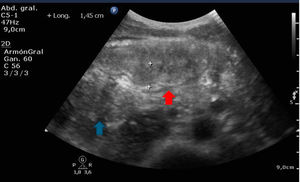

Varón de 31 años sin antecedentes de interés que ingresa por cuadro de varios días de evolución de deposiciones diarreicas, fiebre y dolor abdominal. En la analítica destaca leucocitosis y PCR elevada. En el coprocultivo la toxina de Clostridium difficile es positiva.

Se realiza ecografía de abdomen (fig. 1) en la que se objetiva inflamación de la pared del intestino grueso (flecha roja) con un grosor de 1,45cm (valor normal 0,3cm) y ausencia de peristaltismo visualizado en vídeo en comparación con el asa de intestino delgado (flecha azul), hallazgos compatibles con colitis que posteriormente se confirma por TC (fig. 2).